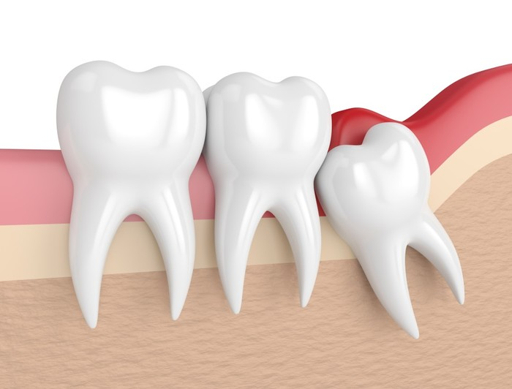

통증을 줄이고 '드라이 소켓(혈전이 떨어져 나가는 부작용)'을

예방하기 위한 식사 가이드

심한 통증과 함께 악취가 나고,

며칠이 지났는데 통증이 오히려

극심해질 때 (드라이 소켓 의심)